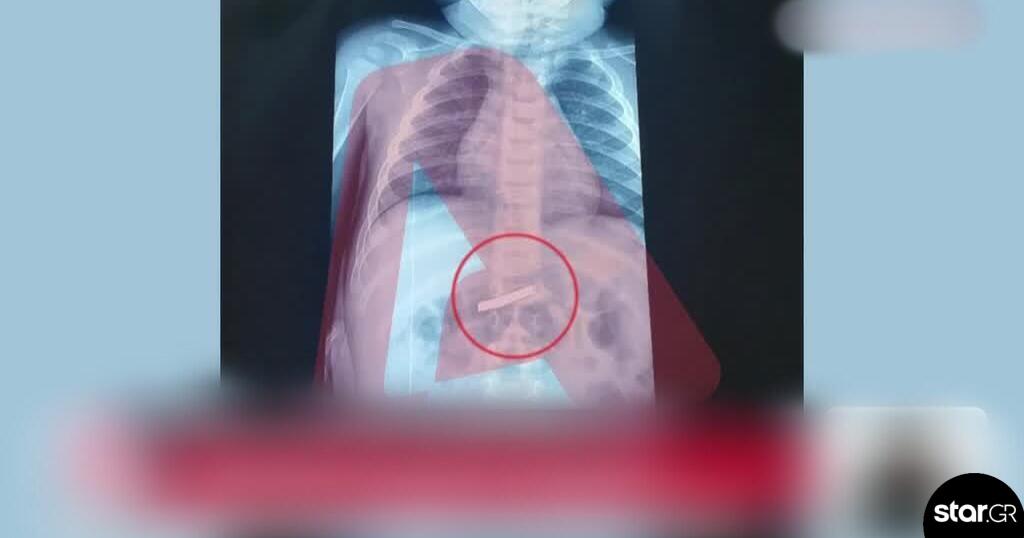

Του έγιναν αμέσως οι απαραίτητες εξετάσεις και ακτινογραφία, η οποία έδειξε ότι το παιδί είχε καταπιεί το αιχμηρό αντικείμενο. Οι γιατροί διαπίστωσαν ότι είχε φτάσει στο στομάχι του 3χρονου και έκριναν απαραίτητο να γίνει άμεσα χειρουργική επέμβαση.

Σύμφωνα με πληροφορίες που μετέδωσε ο Alpha, το αγοράκι υπεβλήθη σε χειρουργείο και το αντικείμενο αφαιρέθηκε με επιτυχία, με το παιδί να έχει διαφύγει τον κίνδυνο.